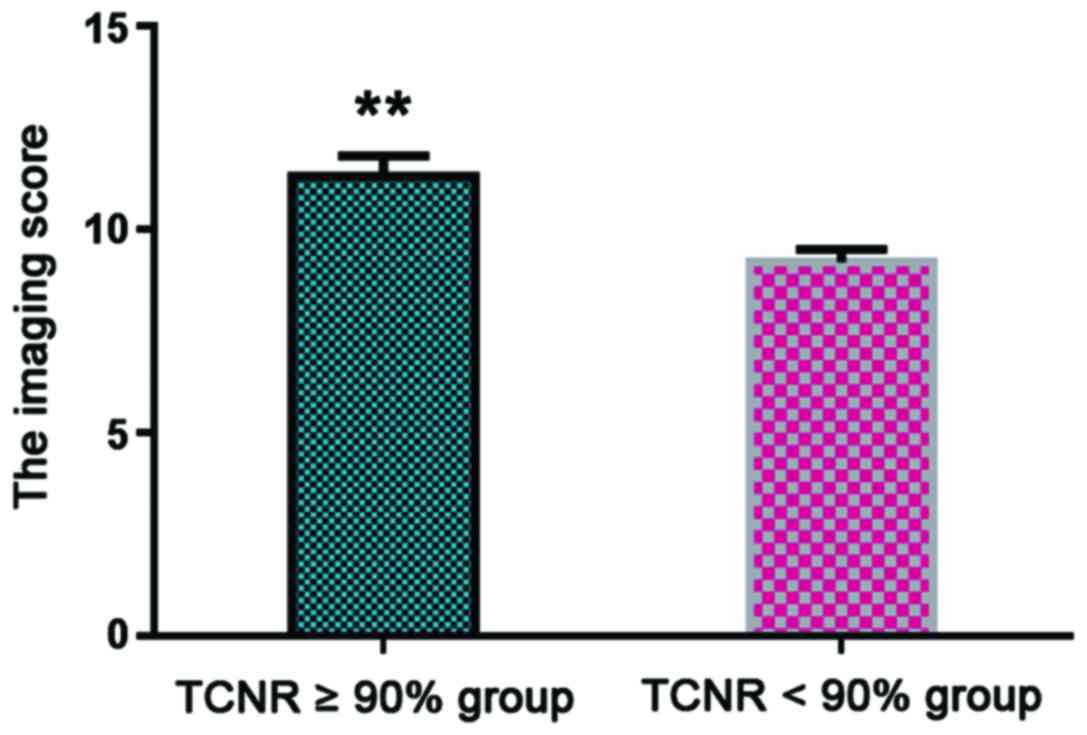

The relationship between imaging score

changes and TCNR after chemotherapy

A TCNR ≥90% indicated good patient prognosis

(7). Patients were divided into TCNR

≥90% (n=21) and TCNR <90% groups (n=9), with statistical

analysis showing that the average imaging score of the TCNR ≥90%

group was 11.3±0.5 points, which was significantly higher than that

of the TCNR <90% group (8.7±0.3, P<0.05) (Fig. 3).

images, we found that the imaging scores of all 30 patients

significantly increased after chemotherapy (P<0.05). The

radiographic score of the TCNR ≥90% group was significantly higher

than that of the TCNR <90% group (P<0.05), suggesting that

imaging score was positively correlated with TCNR, and accordingly,

with improved patient prognosis. Therefore, imaging-detected

characteristic changes can be used to predict patient chemotherapy

effectiveness, thus providing a theoretical basis for clinical

treatment (19).